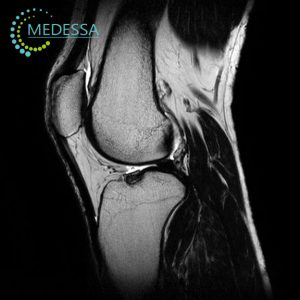

МРТ-діагностика в медичному центрі MEDESSA